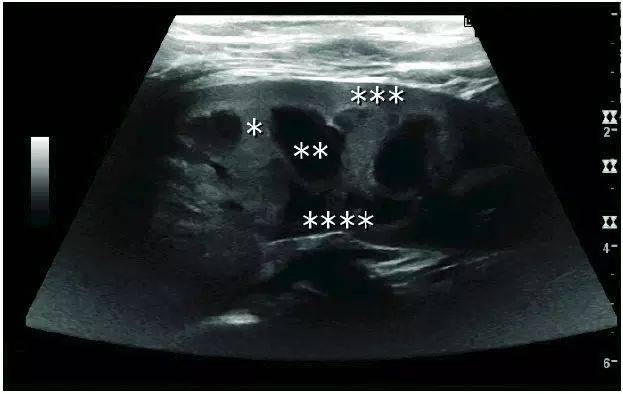

超声入门:肾结石超声诊断

长不大的肾肿瘤 - 超声医学讨论版 - 爱爱医医学论坛

一例后肾腺瘤超声表现病例分析

各类肾脏病超声图像表现